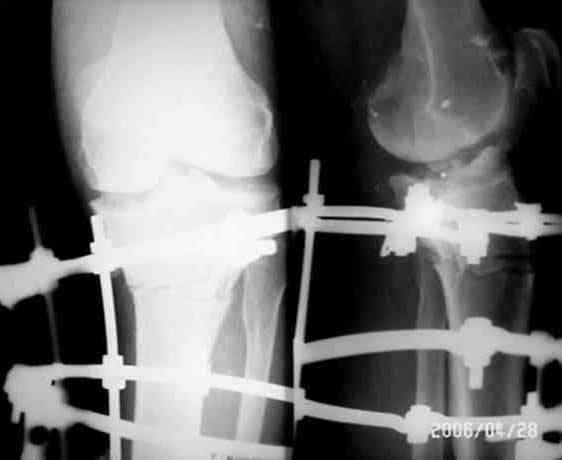

Уважаемые коллеги! Хотелось бы обсудить на форуме ряд вопросов касающиеся оперативного лечения гонартроза и, в частности, высокую остеотомию б/б кости. Работаю в частной клинике ортопедо-травматологического профиля, делаем артроскопические операции, в том числе и при гонартрозах. При варусной деформации сустава выполняем чрез- подбугорковые остеотомии по Илизарову (ВКДО) - как вариант медиальной клиновидной плюс-остеотомии с пересечением латеральной кортикоспонгиозной части кости. Остеотомия (кортикотомия) производится через 1-2 прокола «глазным» долотом (шириной 5 мм) после установки 3 кольцевого гибридного аппарата (спицы 2 мм и стержни 4,5 мм). На крайних кольцах по две спицы с захватом м/б кости, по стержню Шанца в верхнее и среднее кольцо. Пересечение малоберцовой кости производим на протяжении средней трети кости этим же долотом. Первым этапом операции выполняем артроскопическую санацию, дебридмент и т.д. При выращивании клиновидного регенерата центр вращения - наружный кортикалис. Коррекцию начинаем на 5 сутки, завершаем через 10-14 дней. Аппарат снимаем обычно на 45 сутки. Операция непростая, можно ожидать все, что угодно, но очень эффективная. Вопросы: • Возможность применение аутотрансплантата после одномоментного устранения деформации, для того, чтобы не выращивать регенерат и сократить сроки пребывания в стационаре • Возможно, ли выполнение неполной кортикотомии б/б кости с оставлением интактным латерального кортикалиса • Обязательно ли пересечение м/б кости при ВКДО • Есть ли у кого опыт коммерческого лечения больных старше 60 лет с клиникой повреждения менисков на фоне ярко выраженного гонартроза. Наш опыт горький. Прилагаю иллюстрации, Р-граммы - в процессе лечения Попов Виктор, г.Караганда

> опыт горький. Прилагаю иллюстрации, Р-граммы - в процессе лечения